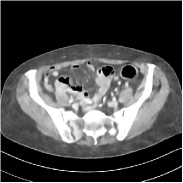

Fig. 3 illustrates the image evolution over SUPER layers (i.e., with evolving network weights in the iterative reconstruction process) for one test case, when using SUPER-WRN-ULTRA. It is apparent that in the early SUPER layers, the proposed SUPER-WRN-ULTRA method mainly removes noise and artifacts, while later SUPER layers mainly reconstruct details such as the bone structures shown in the zoom-in box. A similar behaviour is observed with FBPConvNet-based SUPER methods, which are shown in the supplement (Figs. 13 and 14).

Refer to caption Refer to caption Layer 1RMSE =27.44 HURefer to caption Refer to caption Layer 5RMSE = 26.03 HU

Refer to caption Refer to caption Layer 11RMSE = 25.91HURefer to caption Refer to caption Reference

Figure 3: Image evolution over SUPER layers using the SUPER-WRN-ULTRA method. RMSE values are also indicated.